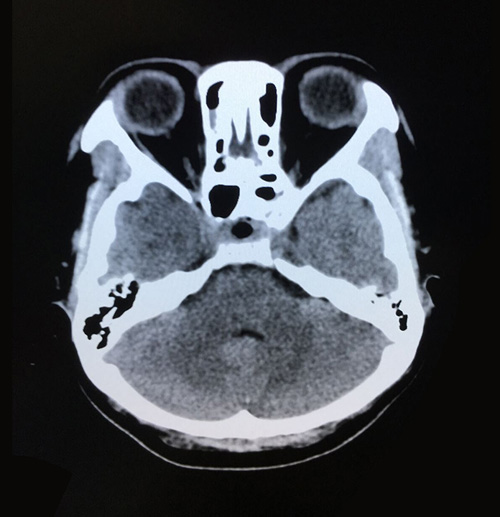

术前影像:垂体大腺瘤,超蝶鞍生长

术后影像:两侧大脑,小脑及脑干形态如常,脑沟脑池未见异常